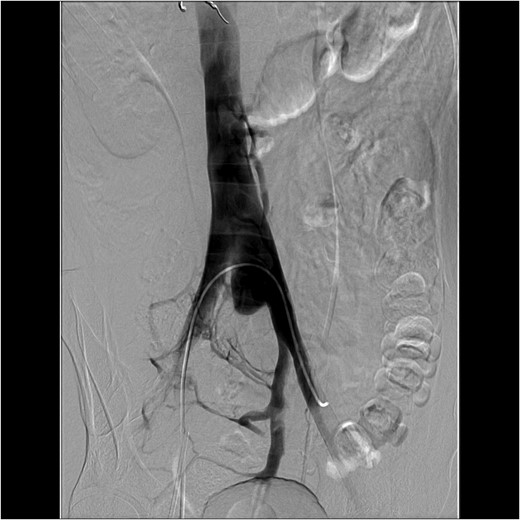

Figure 2:

An interventional radiology angiogram and venogram on Day 1 showed a 2.8 cm pseudoaneurysm in the proximal portion of the left common iliac vein. There was no involvement of the base of the IVC and no active extravasation.